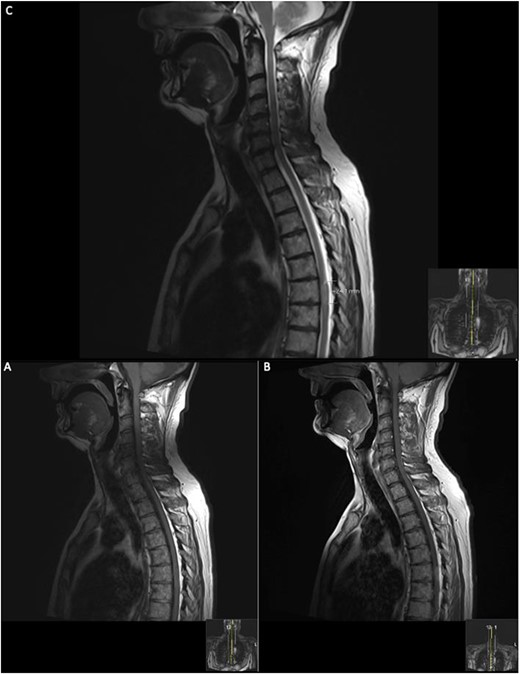

Biopsy demonstrated a well-demarcated tumour with a storiform growth pattern composed of spindle tumour cells with mild nuclear pleomorphism. Intracellular and extracellular deposits of melanin were noted with occasional mitotic figures. Immunostaining for HMB-45 was positive, and ki67 proliferative index was estimated at 5%. Immunostaining for GFAP, STAT6 and EMA was negative. Methylation profiling resulted in the classification of melanocytoma [4] with a calibrated score of 0.99, further supporting the morphological diagnosis of meningeal melanocytoma (Fig. 4).

Histopathological examination with haematoxylin and eosin staining reveals a tumour with a storiform pattern (A) and widespread melanin pigment deposition (B). Immunostaining for HMB45 is positive in the tumour cells (C); the Ki67 proliferative index is estimated at 5% (D); the scale bar corresponds to 100 μm (A, C) and 50 μm (B, D); copy number assay derived from the methylation array suggests a gain of Chromosome 6p (E).